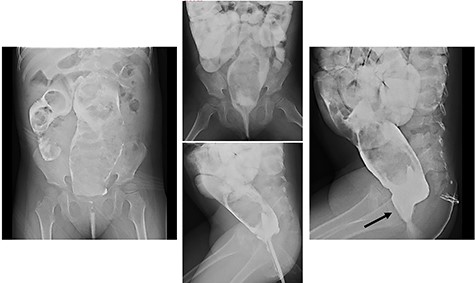

We report herein a case of a 4-year-old girl with ultrashort-segment HD (USHD). She was born at 29 weeks gestation from a twin pregnancy. Her birth weight was 1013 g. After birth, she was administered glycerin enemas to facilitate defecation. Thereafter, she was medicated with sodium picosulfate hydrate for chronic constipation, but she passed stool once in 4–5 days. When she was 4 years old, she was medicated with polyethylene glycol electrolyte solution (MOVICOL® [macrogol 4000]; EA Pharma Co., Ltd, Tokyo, Japan) in another hospital for chronic constipation. After she drank the MOVICOL® twice, her abdomen distended rapidly without passing stool, and she was transported to a hospital. An abdominal X-ray showed a stored stool mass (Fig. 1). A barium enema study revealed dilatation from the rectum to the sigmoid colon due to the stool mass and the rectum was smooth with funnel-shaped tapering toward the anus when she forced herself to defecate (Fig. 2). USHD was suspected, so she underwent anorectal manometry, which showed negative normal reflux. A surgical rectal full-thickness biopsy was performed 2 cm proximal to the dentate line under general anesthesia, which revealed very few ganglion cells in Auerbach’s plexus (Fig. 3a–c). She was suspected to have HD and underwent a Soave endorectal pull-through with an oblique anastomosis, where the pulled-through bowel was anastomosed posteriorly 0.5 cm from the dentate line, laterally 1.0 cm from the dentate line and anteriorly 1.5 cm above this point (Fig. 4). The posterior wall of the aganglionic anorectum was split longitudinally to the level of the dentate line. The resected specimen showed sparse ganglion cells with small cytoplasm in Auerbach’s plexus of the mucosectomy in the rectum (Fig. 5 ①, a and b). In the sigmoid colon of the resected specimen, most of the ganglion cells had scanty cytoplasm, whereas occasional ganglion cells with abundant cytoplasm were visualized (Fig. 5 ②, c and d). She passed stool 4–10 times a day for 6 months postoperatively, but the frequency of passing stool gradually deceased to once or twice a day without anastomotic strictures. Defecation was controlled without medications for 12 months postoperatively.

Barium enema: barium enema revealed dilatation from the rectum to the sigmoid colon due to a stool mass and the rectum showed a smooth funnel-shaped tapering toward the anus when she forced herself to defecate (black arrow: funnel-shaped tapering).

To diagnose HD, a barium enema study can reveal the transition zone between the aganglionic distal segment, which is narrow or of normal caliber, and the dilated proximal colon with normal ganglion cells. The transition zone to the dilated segment is often characterized as funnel-shaped or an inverted cone. Although the transition zone can be a very reliable sign, non-visualization of this sign does not rule out HD [1]. In classifying HD, USHD is only involved at the distal part of the rectum.